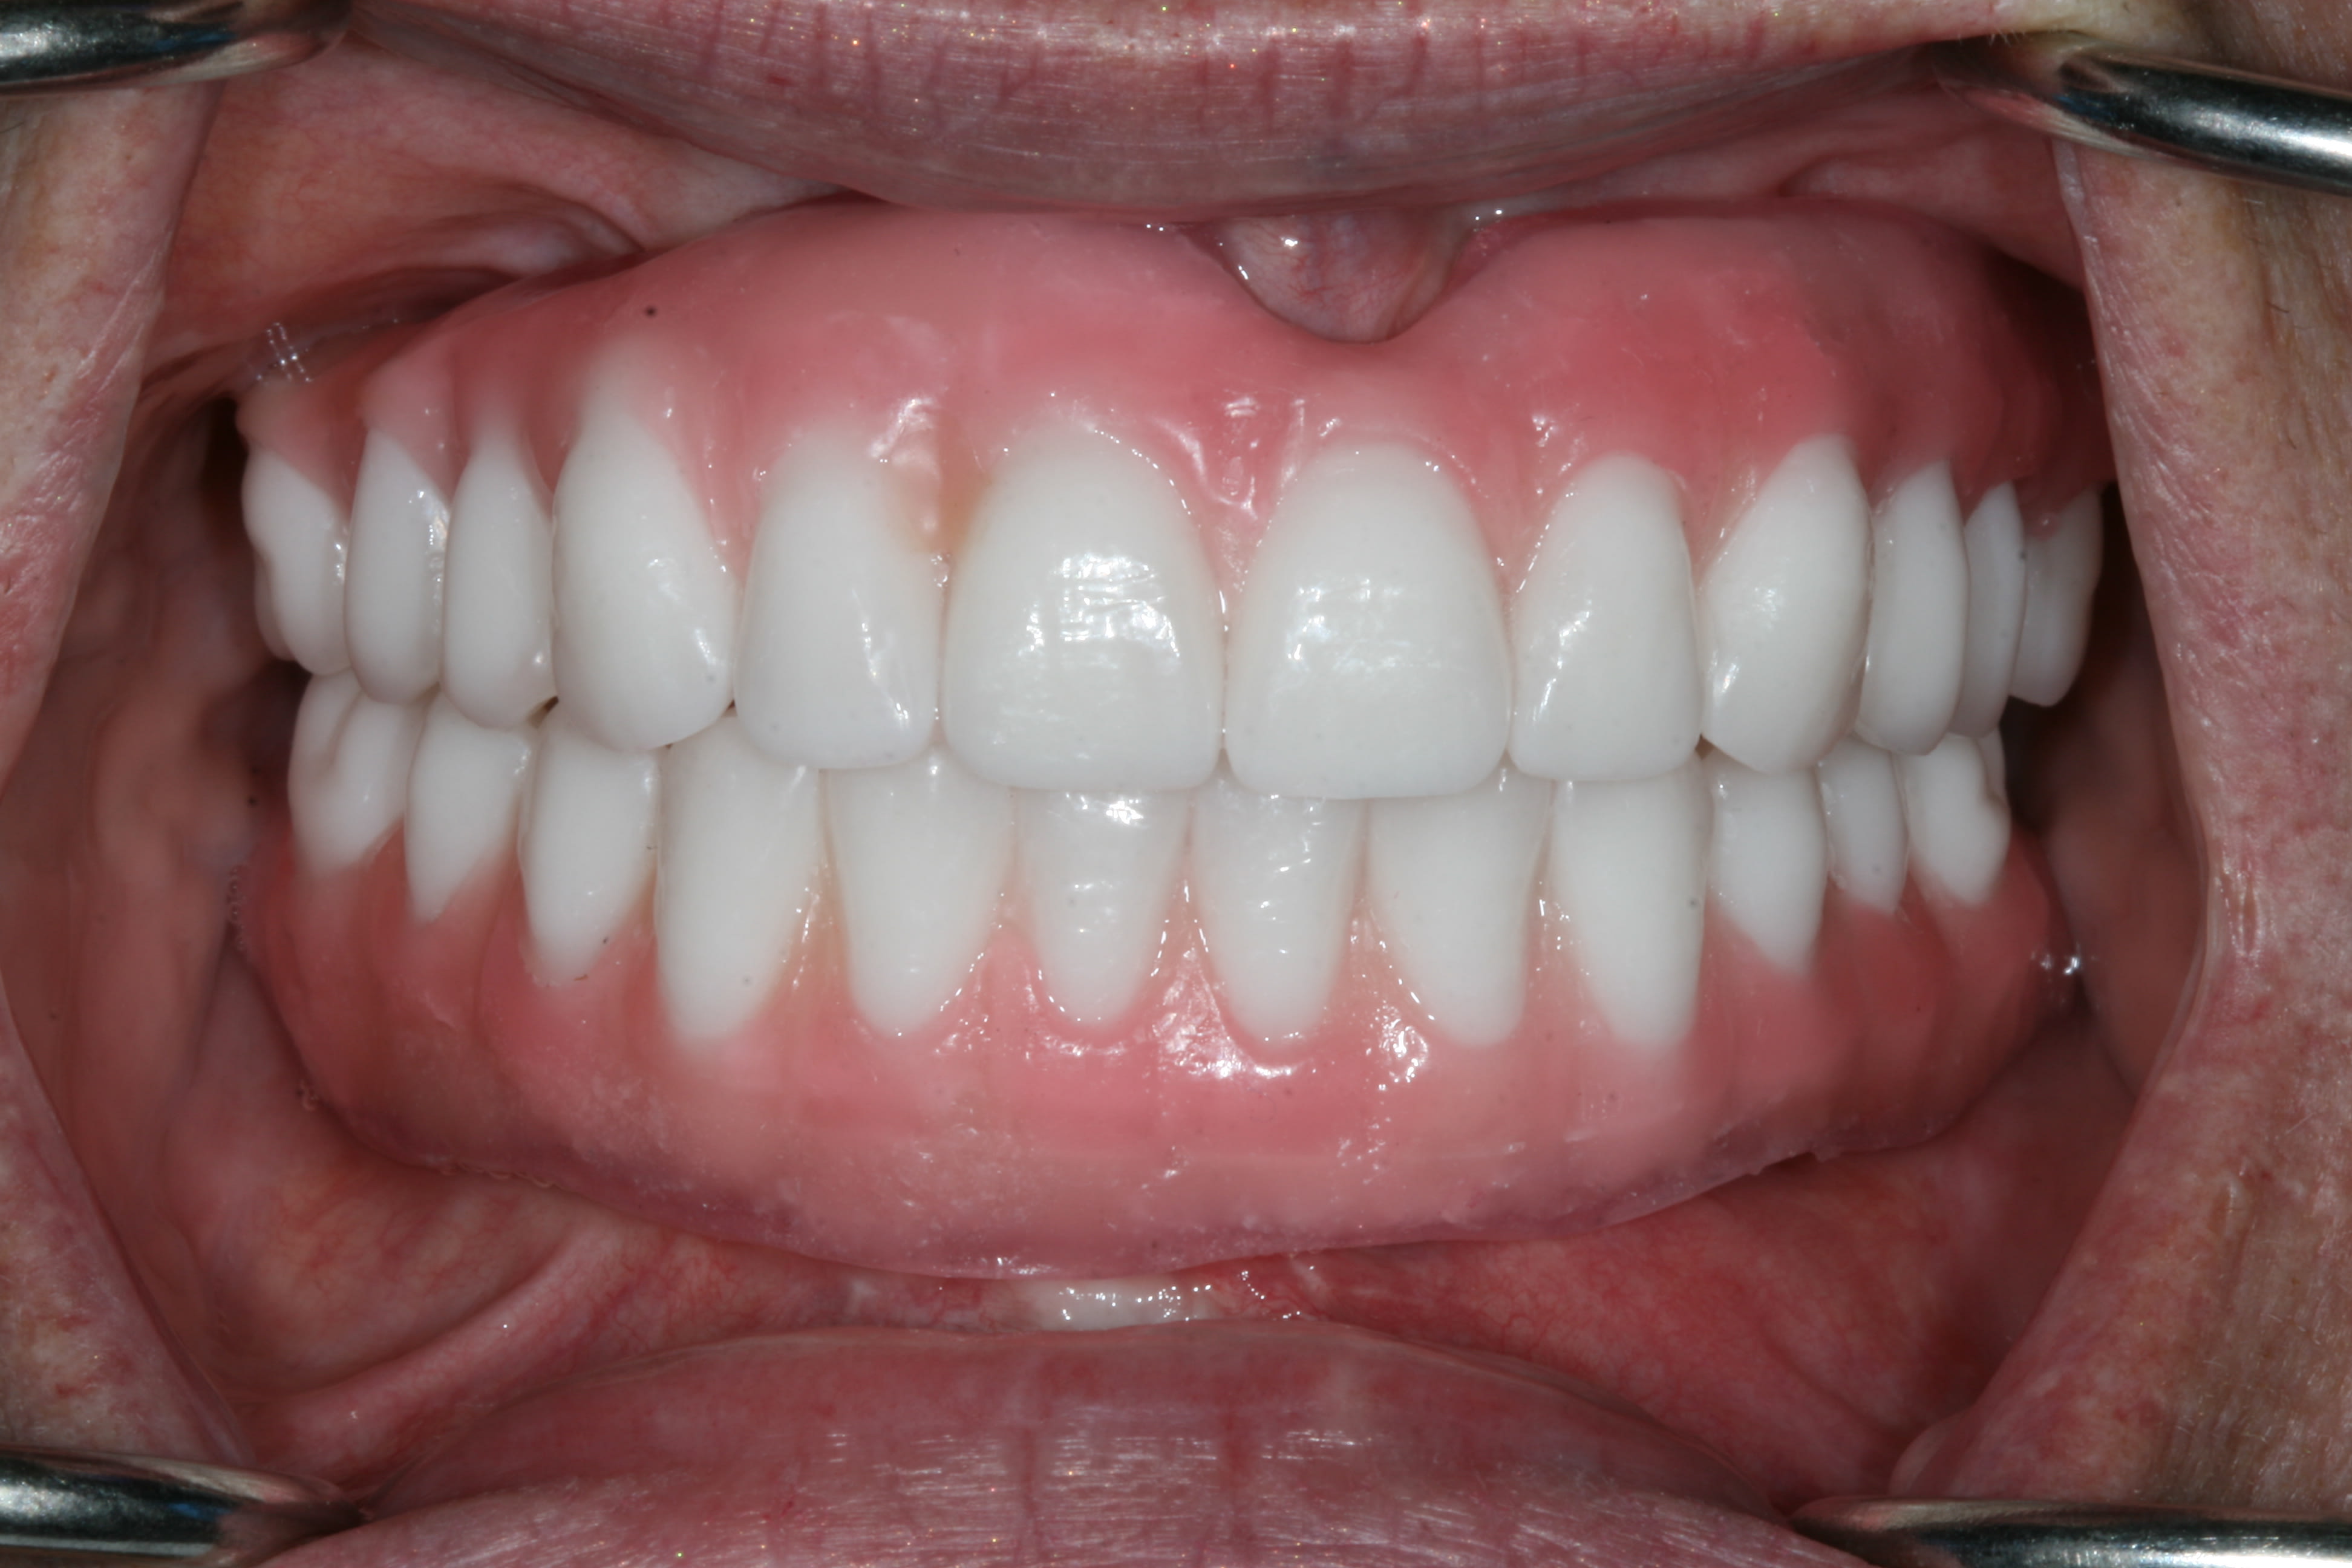

The next afternoon, the prostheses were inserted (Figure 10) and panoramic radiographic confirmation of proper seating was obtained (Figure 11). Any necessary occlusal adjustments were then completed. The patient was given written instructions to be on a very soft diet for the first 4 weeks, after which a normal diet could resume. The patient was then seen every 2 to 3 weeks for deplaquing and plaque control review, per the protocol outlined earlier. The occlusion was also refined as needed. The patient was given a water irrigation device and reviewed at 6 weeks post-surgery.

At the insertion appointment, the healing caps were removed and cleaned with chlorhexidine. Once the prosthesis was inserted, the esthetics, phonetics, and OVD were confirmed, and the occlusion adjusted as needed. Screws were tightened to 15 Ncm and screw-access openings were filled with Teflon tape to within 2 mm of the surface. A soft material such as Telio® or Fermit™ (Ivoclar Vivadent, www.ivoclarvivadent.com) can be used to seal the access. A maxillary acrylic nightguard was fabricated to aid in protecting the occlusal surfaces from wear and to help reduce any parafunctional habits. Figure 15 through Figure 18 show the completed case.